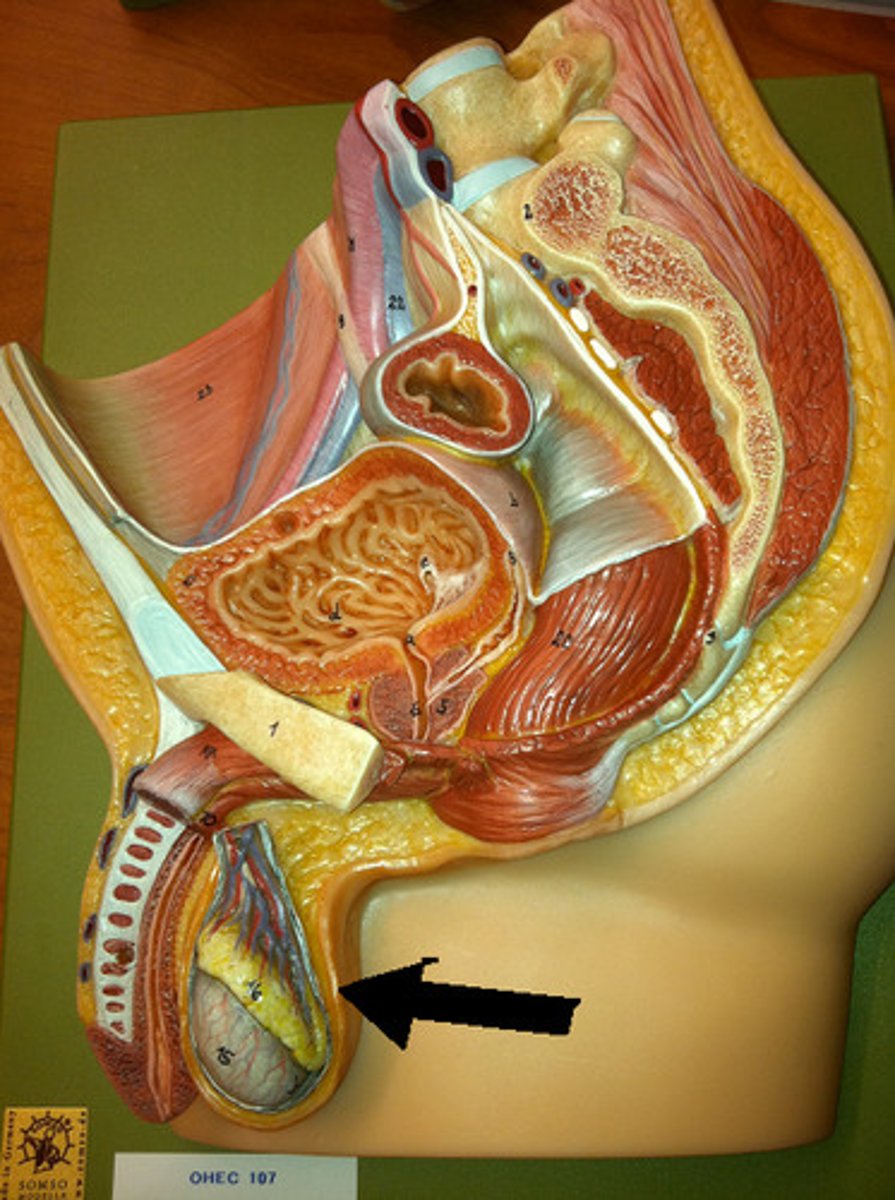

Scrotum

Testis (testes)

Tunica albuginea

Tunica vaginalis

Seminiferous tubules

Lobule

Septum

Rete testis

Efferent ductule

Epididymis

Spermatic cord

Ductus deferens

Prostate gland

Bulbourethral gland

Urethra

Penis